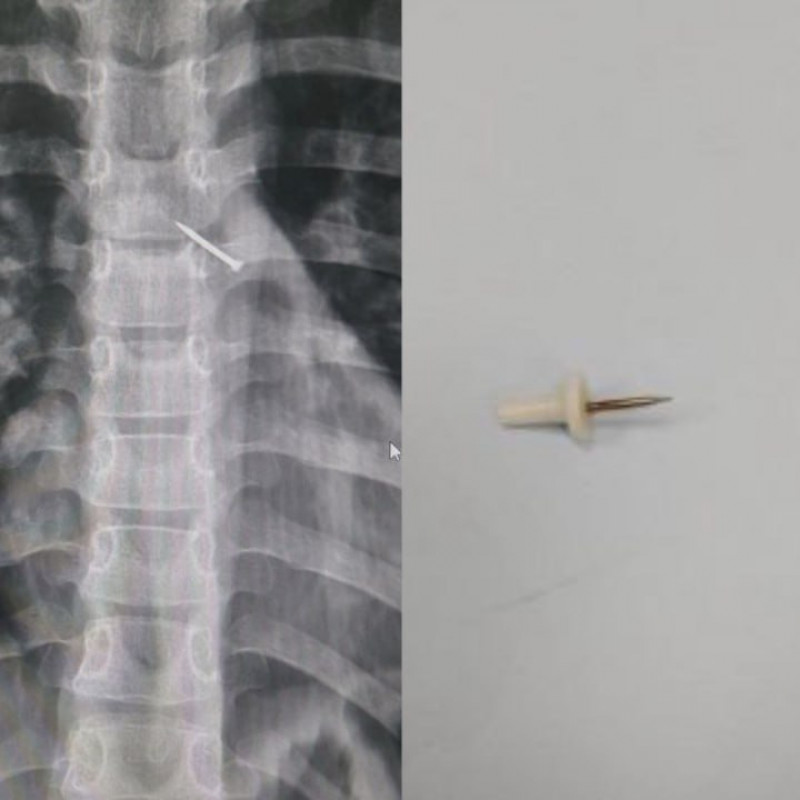

Врачи выяснили, что внутри мальчика находится канцелярская кнопка и она уперлась в стенку бронхов. Инородный предмет успел вызвать воспаление.

Оказалось, что он случайно вдохнул острую кнопку.

С помощью эндоскопических зажимов кнопку предмет вытащили. А через четыре дня ребенка выписали абсолютно здоровым.